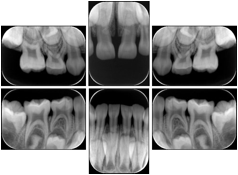

2. A patient requests cosmetic surgery to enhance their facial appearance. The case requires consultation between an orthodontist in New York and an oral surgeon in California. The cephalometric series of 2D projections constructed from the volumetric CT data that is used for the discussion is arranged by a Structured Display for transfer between the two practitioners.

Cephalometric Series Structured Display

Figure OO-2. Cephalometric Series Structured Display